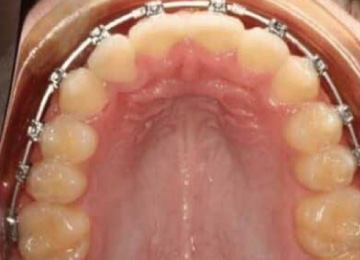

Брекеты: фото До и После

Внешне брекеты выглядят почти одинаковы, однако могут отличаться по способу крепления:

- для безлигаторных брекетов креплением выступает закрывающаяся защелка со специальным пазом.

Источником давления, благодаря которому и осуществляется коррекция, выступает упругая дуга. Этот элемент брекетов задает постоянную силу давления, но отличается эластичностью, поэтому если положение изменилось, дуга все равно вернется в исходное.